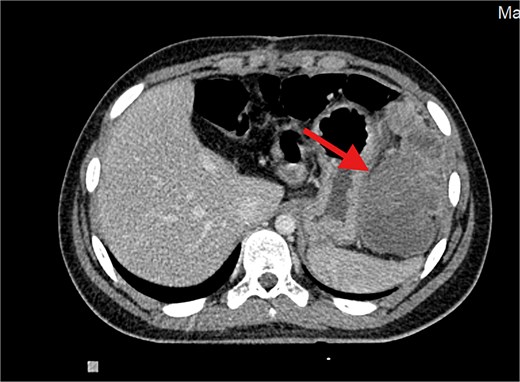

The patient underwent left lateral hepatectomy and cholecystectomy following diagnosis. Histopathology confirmed undifferentiated embryonal sarcoma (UES) of the liver with a 1 mm clear margin (Fig. 1); immunohistochemistry supported the diagnosis. The gallbladder showed chronic cholecystitis, and the lymph nodes were tumor-free. Postoperative imaging after two months revealed a recurrent mass near the stomach (Fig. 2), confirmed as recurrent UES by biopsy. Re-excision showed extensive necrosis and peritoneal infiltration. Positron emission tomography – computed tomography (PET-CT) later identified peritoneal and mesenteric metastases (Fig. 3). Follow-up PET-CT also revealed multiple small hypermetabolic hepatic nodules in addition to peritoneal and mesenteric lesions, indicating intrahepatic disease recurrence. Six cycles of chemotherapy resulted in near-complete resolution of metabolic lesions, with minimal residual activity. Follow-up imaging showed near-complete resolution of hepatic nodules, with only one residual, non-suspicious tiny nodule. After additional chemotherapy and targeted therapy cycles, PET-CT revealed new focal hypermetabolic activity near the splenic flexure, anterior to the spleen, raising concern for recurrence (Fig. 4). The patient underwent omentectomy and splenectomy. Histopathology confirmed metastatic UES in a 2.5 cm splenic lesion with hemorrhage and necrosis, and a 0.4 cm omental nodule, both completely excised. A total of 15 chemotherapy cycles were completed. Post-treatment imaging showed a mixed-density lesion in the splenic bed with FDG uptake, possibly post-surgical, and a new hypermetabolic mesenteric nodule (Fig. 5). Magnetic resonance imaging showed a cystic post-surgical collection without enhancing lesions. Subsequent imaging revealed regression of the splenic bed lesion and resolution of the mesenteric nodule; however, a new hypermetabolic mesenteric density emerged (Fig. 6). The lesion was placed under active surveillance, with additional chemotherapy administered and repeat imaging scheduled to assess response. Bilateral axillary lymph nodes showed reactive hypermetabolism. The patient, having undergone hepatectomy, splenectomy, and multimodal therapy, remains under close surveillance with encouraging treatment response.

Contrast-enhanced axial CT image showing a large, heterogeneously enhancing soft tissue mass measuring ⁓11 × 5.5 × 8.3 cm in the left subphrenic region, abutting, and indenting the greater curvature of the stomach. The lesion demonstrates internal cystic and necrotic components, consistent with a recurrent undifferentiated embryonal sarcoma.